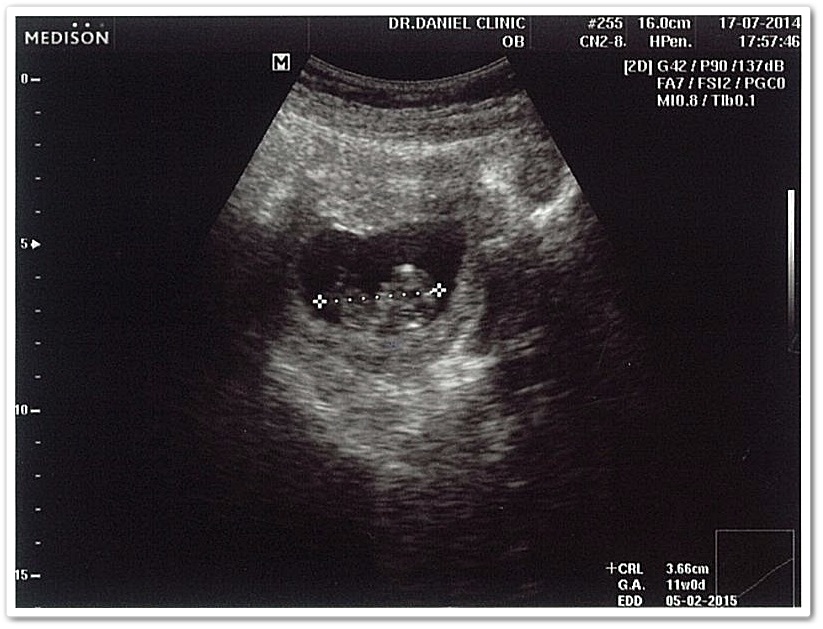

อวดภาพอัลตร้าซาวด์ครั้งที่ 2

นี่คือภาพอัลตร้าซาวด์ครั้งที่ 2 ที่เพิ่งไปซาวด์มาสดๆ ร้อนๆ อายุครรภ์ครบ 2 เดือนครึ่ง (ส่วนภาพแรกลืมถ่ายเก็บไว้ 555)

ยิ่งโตขึ้น โตขึ้น การไปตรวจแต่ละครั้งก็เห็นพัฒนาการของเทวดา นางฟ้าตัวน้อย ที่อยู่ในพุง